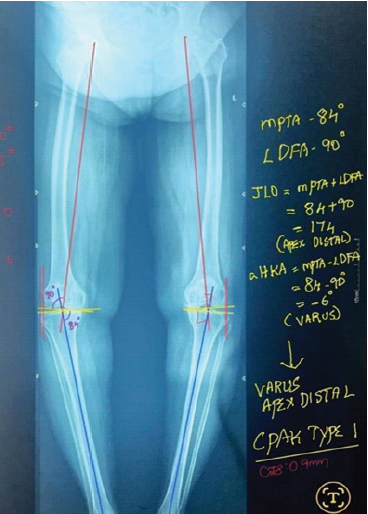

Coronal Plane Alignment of the Knee Classification and Its Correlation with Post-operative Functional Outcomes in Total Knee Arthroplasty: A Prospective Cohort Study

Siddharth Malik , Gourab Biswas , Nithin Sundaresan , Sitansu Sekhar Samantaray , Akash Pradip Bera , Hunaid Zoeb Haider

………………………………p.354-363